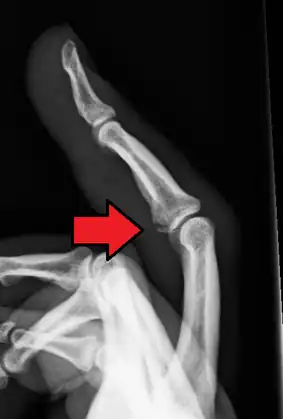

| Avulsion fracture of a fingertip bone | |

The evaluation of avulsion fractures is generally done via Xrays.[6]

Avulsion fracture of the proximal middle phalanx on the palm side